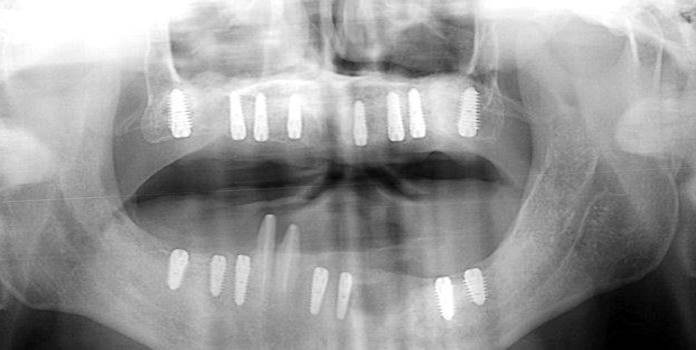

Clinical case: Full-mouth implants for mandibular & maxilla - restored using mixed prostheses

- Courtesy of Dr. Hyun Jun Kim, Korea -

Keywords

AnyRidge, full-mouth implants, mandibular, maxilla, edentulous, full mouth rehabilitation, Octa abutment, long-term clinical case, biological stability, Dr. Hyung Jun Kim